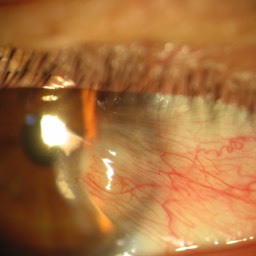

Quelques pathologies ophtalmologiques du segment antérieur